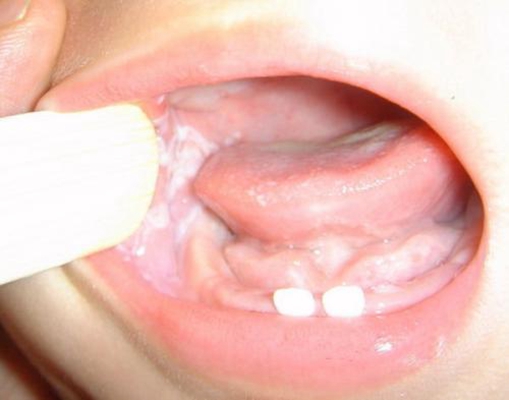

口腔黏膜病圖片

口腔念珠菌感染 (46)